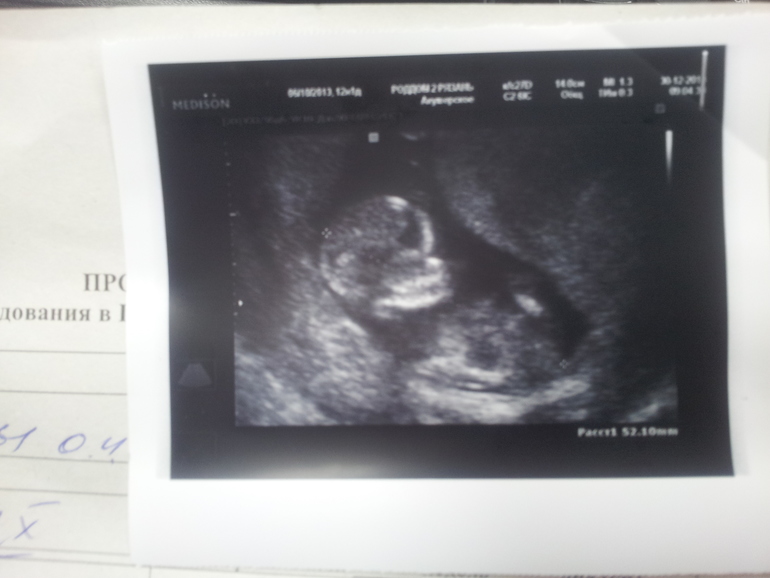

почти такой же снимочек был четкий! сказали что еще рано пол но похоже тоже принцесса Жасмин)))) ручка правая на животике а ножки раскинуты.вот интересно,на таком раннем (12 нед) это кто скорее всего? хотя кто бы ни был(а) мы рады будем!

Боже, какая прелесть)) Такой настоящий человечек))) Скажите, это 12 акушерских недель или от зачатия?

Удивляюсь, как же хорошо ребенка на этом сроке видно! :)А мне ни разу на таком сроке не говорили пол, помню, самое раннее в 16 недель . Надеюсь, у вас не ошиблись )

я тоже недавно была на узи ровно в 12 недель, так четко ребенка видно, причем на обычном аппарате черно белом, даже сердечко видно как стучит))))